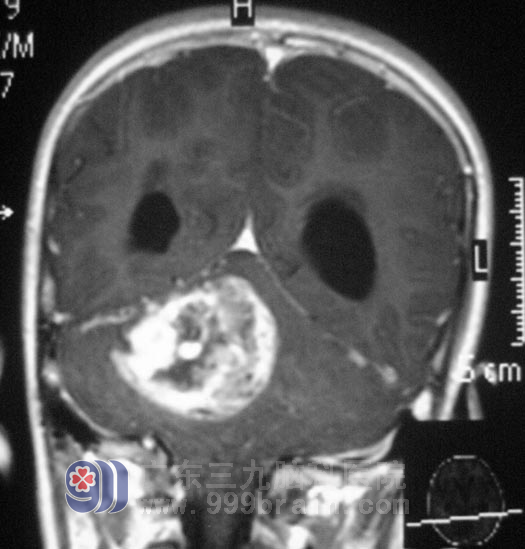

紧急关头,一个杨门女将中的“太君”站出来了,奶奶做出明智的选择——到广州治疗!于是,挎上行李,婆孙俩来到三九脑科医院,找到外科专家鲁明主任,听完了老人家对小海病情的描述,鲁明主任被老人家这种深明大义的精神感动,指示一定尽全力治疗小海。经过缜密的讨论,第一步,给小海行脑室腹腔分流术,解除脑积水症状,待恢复后,在全麻下行右侧小脑半球肿瘤切除术,术中见肿瘤质软、色黄,在显微镜下予肿瘤切除,手术过程顺利,术后小海清醒后未诉不适,经过住院治疗,小海头不痛了,走路不再像喝醉酒似的,又恢复了以前天真乖巧的样子了,小海的奶奶对鲁明主任的手术治疗表示非常满意。术后经病理证实为:(右侧小脑)毛细胞型星形细胞瘤,WHO I级。http://www.999brain.com/

术前